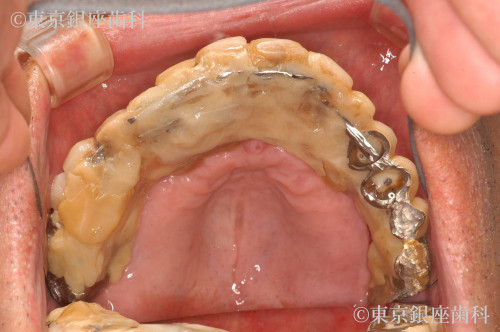

昔行ったインプラントからワンデイインプラントに変更

歯周病が進行したため、上下でワンデイインプラントを実施